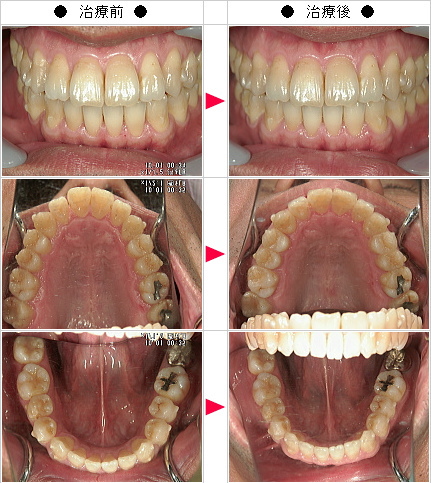

☆出っ歯矯正の治療症例[奥田様 46歳 男性]